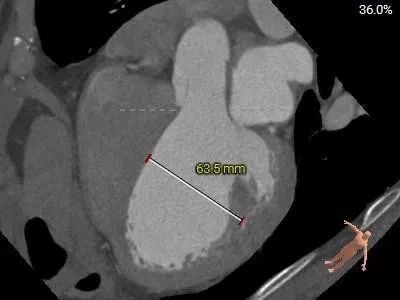

患者男性,因“间断气短5月余,再发10余天”入院,10余天前再发气短不适,活动耐量差。查心脏超声提示:左室(前后径、左右径、长径)83、76、92mm,室间隔:厚度9mm,左心功能:EF:22%。收缩期主动脉瓣前向血流速度正常,Vmax:164cm/s;舒张期期下可见大量反流面积约10.4cm²,容积约18ml。

左心室扩大